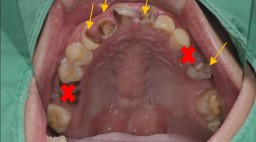

任何治療都必須做審慎評估,表面看見的問題不代表全部。 例如這位陳先生主訴是想門牙做假牙+恢復正常咬合功能。 但檢查做完之後原來沒有想像中容易,牙周/深度齲齒/根管…….等問題一一浮現,要打好基礎,有好的根基才能有穩固的建築。

治療前:前牙蛀洞大,牙齦發炎,殘根,小臼齒蛀牙深,牙齒變色。